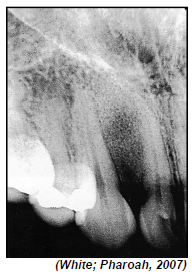

A análise radiográfica da estrutura interna de lesões intraósseas é importante na definição de hipóteses de diagnóstico.

O aspecto radiográfico na imagem radiográfica anterior pode nos sugerir como hipótese de diagnóstico